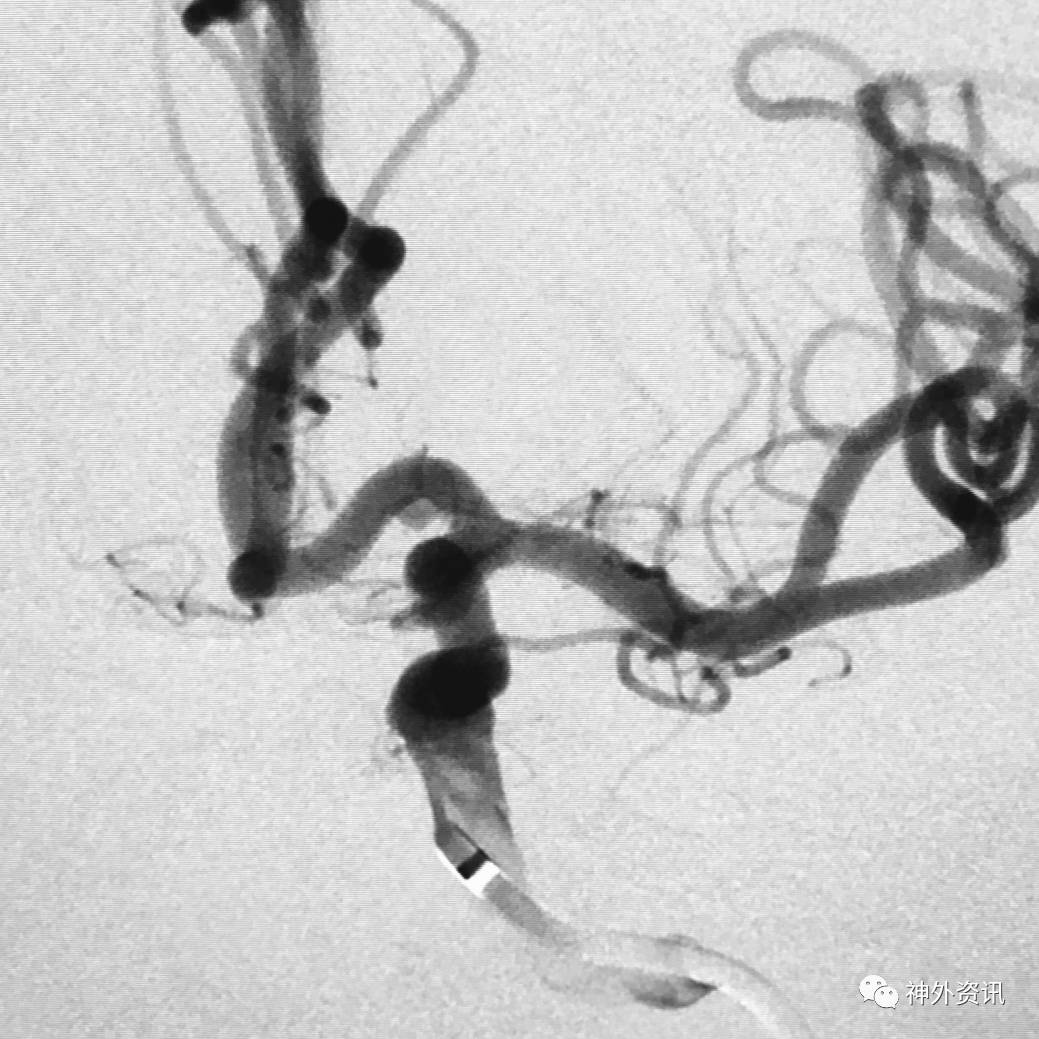

病例一

眼动脉动脉瘤,支架完全释放后,微导管成袢逆行到位

病例二

眼动脉动脉瘤,支架释放前,微导管成袢逆行到位